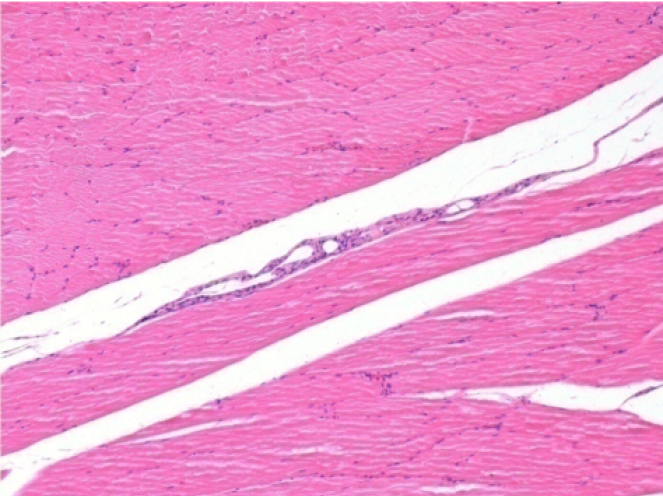

10

Iniezione Endopeel nel tessuto subcutaneo SC

Scatola 6

0.5 ml ( 5x 0.1ml): Iniezione SC di Endopeel nel tessuto pretibiale subcutaneo SC destro (Dx).

Sx:200x-Controllo-SC

Dx-Giorno10-SC-200X

Dx-Giorno30-SC-200X

Dx-Giorno90-SC-200X

Dx-Giorno210-SC-200X

Dx-Giorno210-SC-400X

Endopeel induce una miofibrolisi selettiva reversibile e una risposta infiammatoria approssimativamente nel periodo di 1 mese.

I cambiamenti dei tessuti muscolari sono quasi completamente reversibili.

Il muscolo é il posto migliore per iniettare Endopeel ,per la sua maggiore efficacità, il controllo e la durata della sua azione.

Nessuna necrosi ne ascesso sono stati osservati durante la sperimentazione.